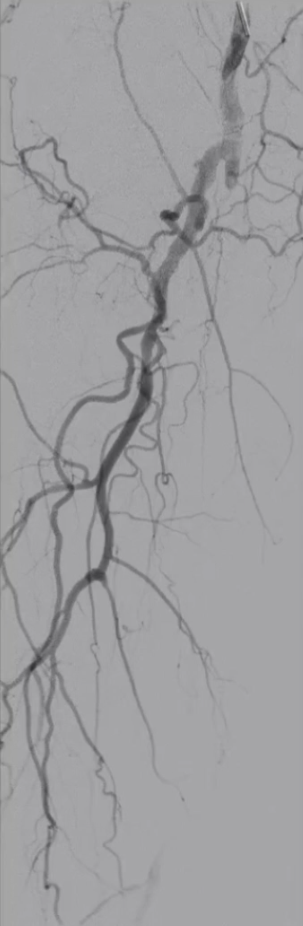

6

手术结果:

血流通畅,解剖与功能双重改善

最终造影显示:支架定位准确、形态良好,股浅动脉、腘动脉及膝下动脉显影清晰,血流通畅。